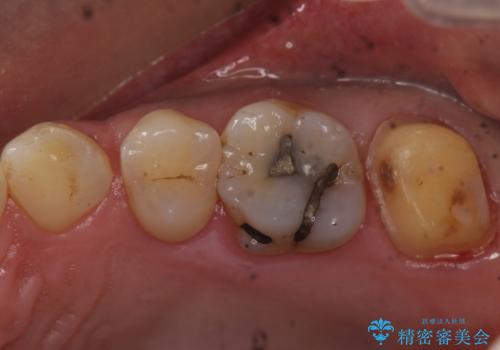

- 奥歯に物が詰まりやすいということが主訴で来院され、歯全体が虫歯になっていたので被せ物にて治療を行なった。

仮歯を装着した時点でものが挟まる症状は改善されました。

虫歯は綺麗に取り切れています。